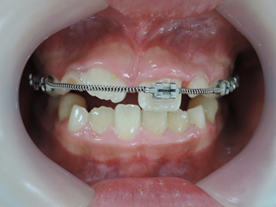

はじめに目立たないブラケット(歯に付ける矯正装置)を利用して上顎から歯並びを改善します。その折に同時にレジンを利用する事で咬み合わせの高さも挙上していきます。

歯並びを改善すると受け口がひどく見える時もありますが心配ありません。

次にMEAW(マルチループ)を利用する事で咬み合わせの高さや咬み合う平面の角度を変える事で歯(第一小臼歯)を抜く事無く受け口(下顎前突)を改善していきます。

また、MEAW(マルチループ)はゴムを24時間使用する事で最大の効果を発揮することが出来ます。

外傷症例には早期に矯正装置(ブラケット)を装着していきます。

そのことで保定効果を期待します。また、外傷によって変わってしまった歯の位置を元に戻すことが出来るからです。

その後、下顎にも矯正装置を装着して歯並びを綺麗にしていきます。

その後、MEAW(マルチループ)と顎間ゴムを24時間利用する事で受け口(下顎前突)と歯並びを改善していきます。

☆上顎から矯正装置を装着していきます。

☆上顎の歯が揃ってから、下額に矯正装置(ブラケット)を装着します。